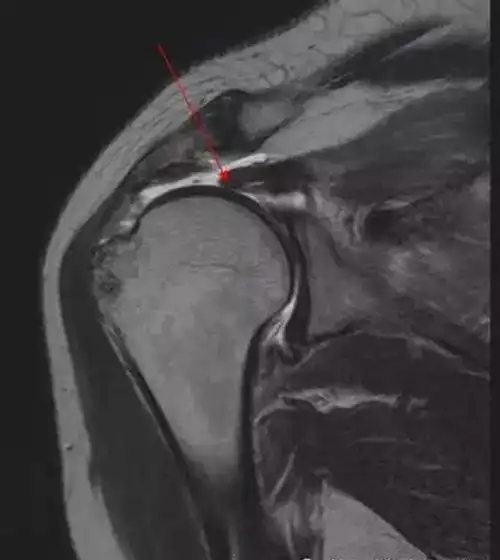

肩袖解剖及损伤的临床及mri诊断

肩袖损伤的mri诊断技巧

肩关节肌腱病一文读懂肩袖损伤的磁共振分级

【医学科普】肩袖损伤的mri诊断技术

肩袖损伤mri诊断影像天地